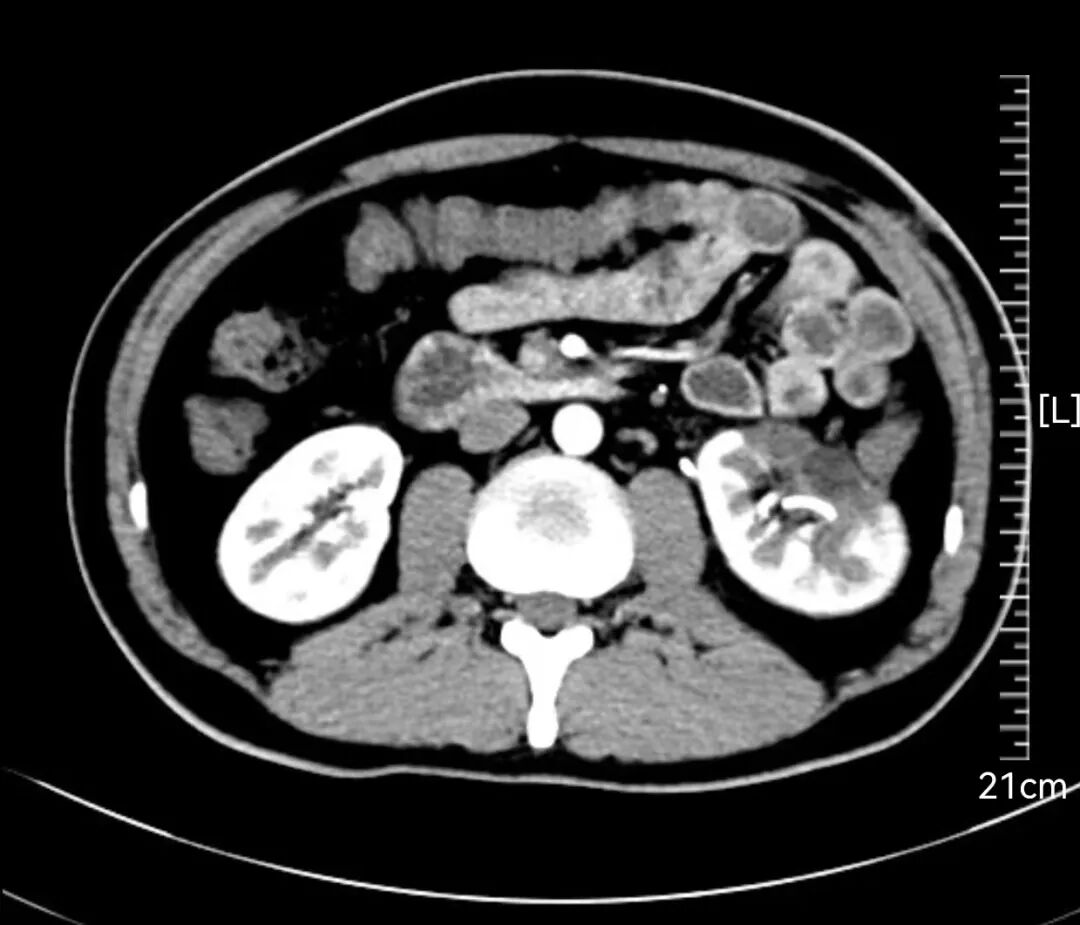

患者文先生在一次常规体检中,意外发现左肾存在一个巨大占位。进一步的增强CT检查结果令人倒吸一口凉气:一个大小约93×82×90mm的类圆形肿瘤从肾脏突出,位置极其凶险,紧贴着肾门部的大血管和集合系统。经专业评估,该肿瘤R.E.N.A.L评分高达11分,属于“高度复杂”级别。